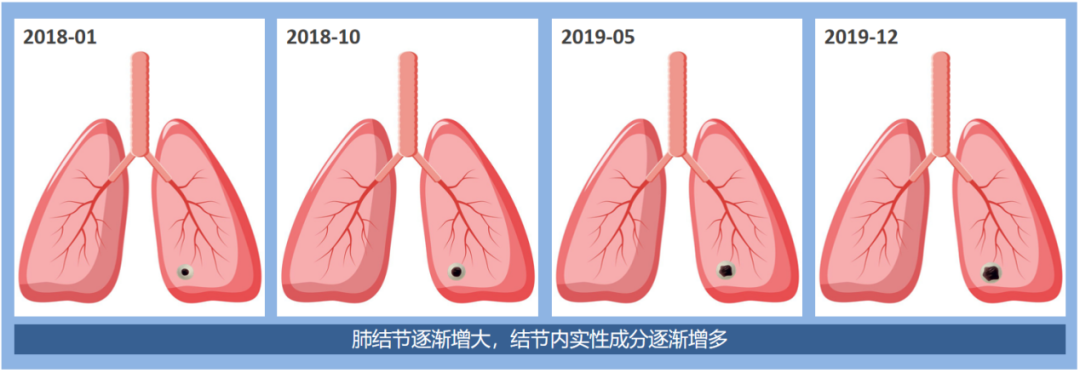

第三组:混杂磨玻璃结节

这是一例混杂磨玻璃结节,我们可以看到随着一次次的随访,结节的大小不断的增大,其中的实性成分也随之增多。该患者术后病理为肺癌。